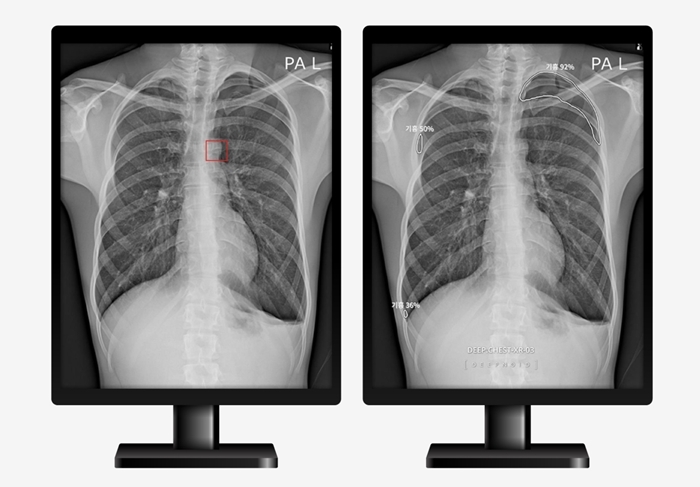

이 논문은 AI가 의사를 도와 사람의 흉부 엑스레이(X-ray) 영상에서 이상 부위를 검출해 질환 진단 결정을 보조하는 딥체스트(DEEP:CHEST)를 고도화시켜 유용성을 검증한 AI 기반 흉부 영상진단서비스와 관련된 내용이다.

회사 측은 이번 논문을 통해 일반적으로 질환에 대한 탐지뿐만 아니라 질환의 정확한 위치 정보까지도 진단결과에 포함한 것에서 기존 진단 보조 제품들과는 차별화를 뒀다고 밝혔다.

최우식 대표는 "의료현장에서 폐질환 진료를 좀 더 효과적으로 진단할 수 있는 동시에 질환의 위치까지 한 번에 제공해 잠재적인 질환까지 도 체크할 수 있는 기회가 됐다"고 말했다.